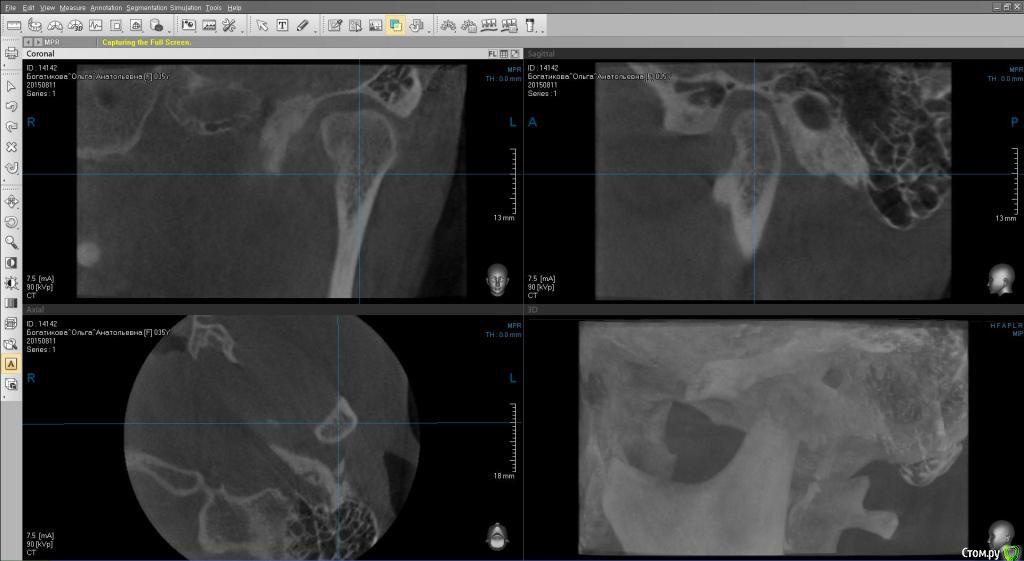

ol"ga Опубликовано 15 августа, 2015 Автор Поделиться Опубликовано 15 августа, 2015 (изменено) Вот еще кт левого и правого внчс, и фото улыбки Изменено 15 августа, 2015 пользователем ol"ga Ссылка на комментарий

Yana guapa Опубликовано 15 августа, 2015 Поделиться Опубликовано 15 августа, 2015 я не вижу у ВАс асимметрии лица, асимметрии верхней челюсти. А вот нижняя челюсть смещена влево, (это видно по ОПТГ и фото), вследствие чего произошло смещение дискав таких случаях обычно1. выравнивают зубные ряды ( с удалением восьмерок) 2. ставят нижнюю челюсть в правильное положение (различными способами, специальные пружины, эластики, форсус, твин форс и т.д.) каждый врач сам для себя выберает, что ему удобнее п.с. похоже что вверху слева ВАм удаляли восьмерку, нго оставили 1 корень. Ссылка на комментарий

Yana guapa Опубликовано 15 августа, 2015 Поделиться Опубликовано 15 августа, 2015 по снимкам - все итак понятно, без подписей.по "щечкам" - Вам скуловые кости никто не двигал, мягкие ткани ортодонт тоже не перемещал, так что это не в юрисдикции ортодонта. вот поворот нижней челюсти - это да, это видно и этим можно заниматься Ссылка на комментарий

Skip Опубликовано 24 августа, 2015 Поделиться Опубликовано 24 августа, 2015 Зубной ряд верхней челюсти СПРАВА выше, чем слева? Ссылка на комментарий